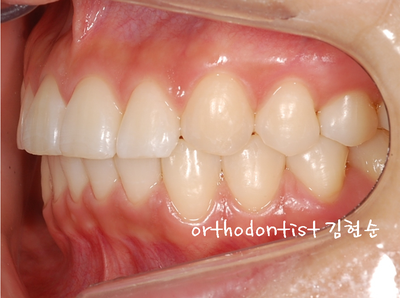

하는 모습입니다

모습으로 변화되어 보입니다

할 수 있습니다